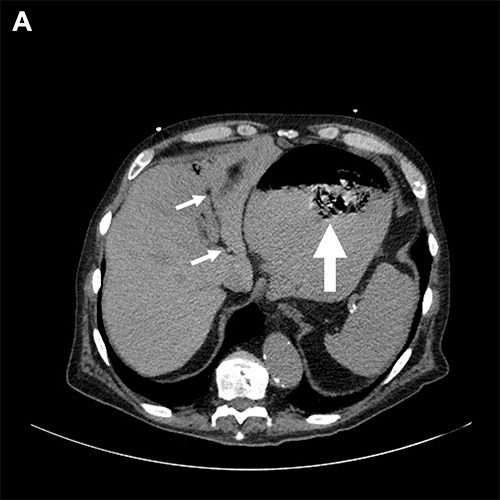

At the initial examination, the patient was alert, oriented, and complaining of severe abdominal pain. He was hypertensive with otherwise normal vital signs and a body mass index of 22. His abdomen was distended, tympanic, and diffusely tender. His laboratory tests included a white blood cell count of 14,400 per µL, a serum bicarbonate of 15 mEq/L, and a serum lactate of 6 mmol/L. Attempts at nasogastric tube placement were unsuccessful secondary to resistance during insertion. A computerized tomography (CT) scan obtained in the emergency department demonstrated (i) markedly dilated loops of small bowel with a transition point in the distal ileum, (ii) portal venous gas, (iii) a small ventral hernia containing a non-obstructed loop of colon, and (iv) a foreign body (possibly a bezoar) freely floating within the lumen of a distended, intraabdominal stomach (Figure 1).

Figure 1. Preoperative CT. Published with Permission

A) Cross-sectional view, upper abdomen. Large arrow = free-floating mass within lumen of stomach. Small arrows = portal venous gas

B) Sagittal view, left side

C) Coronal view, anterior